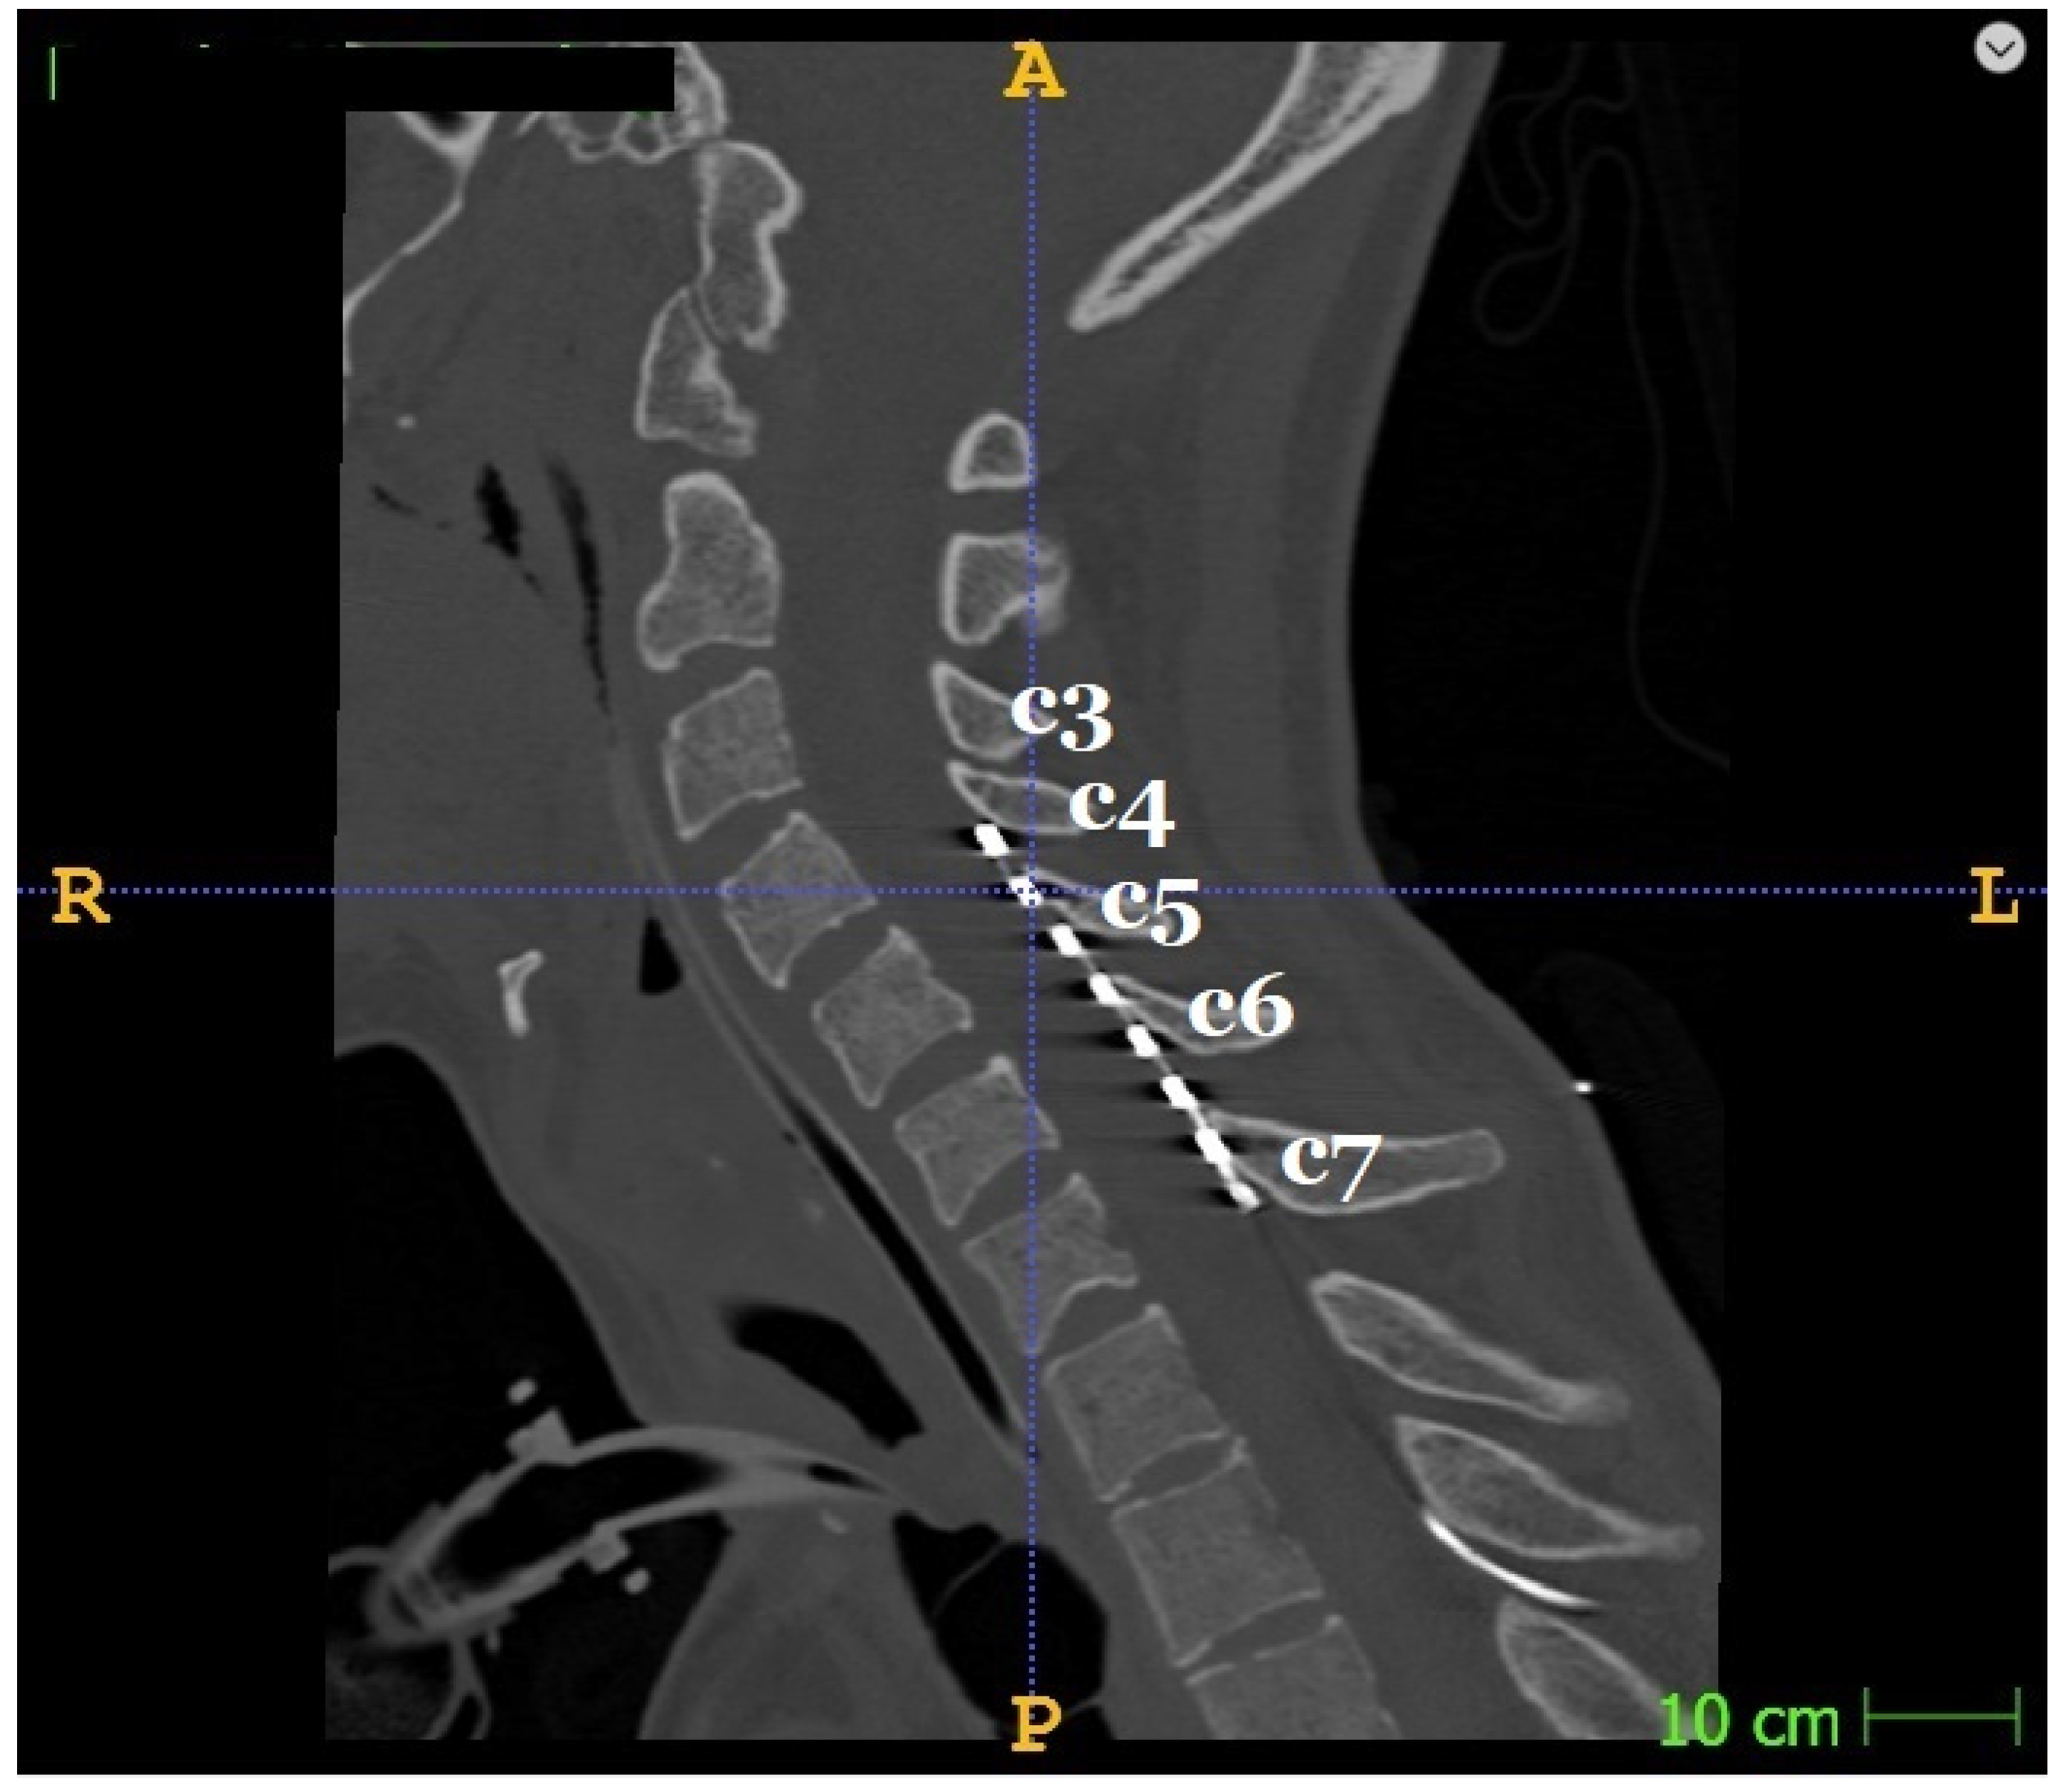

2.5. SCS Therapy: Temporary Electrode Installation and Stimulation Protocol